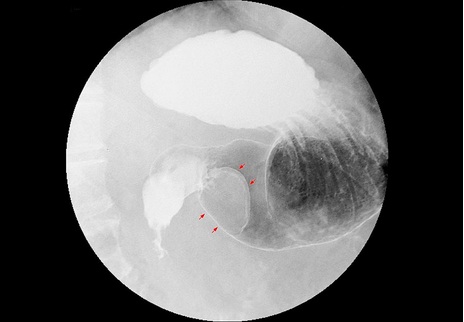

Tumor im Magen

Foto: Magen-Tumor; Hellerhoff CC BY-SA 3.0 (VIA WIKIMEDIA COMMONS)